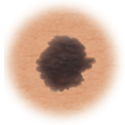

Moles (nevi)

Small skin marks caused by pigment-producing cells in the skin. Moles can be flat or raised, smooth or rough, and some contain hair. Most moles are dark brown or black, but some are skin-colored or yellowish. Moles can change over time and often respond to hormonal changes.

Most moles are benign and no treatment is needed. Some benign moles may develop into skin cancer (melanoma). See below for signs.